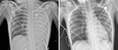

日前,湖南长沙两岁七个月的男童乐乐出现高烧反复不退的情况,起初并没有引起家长注意,仅当做普通感冒治疗。一周后,病情仍在持续加重,还出现了咳嗽不止的情况。经医院检查发现,竟然是腺病毒感染,并已引发肺炎,需要马上住院治疗。类似的情况近期屡见报端,许多家长为此焦虑不安。

据了解,儿童腺病毒肺炎是病毒性肺炎中较常见的一种,多见于6个月-2岁的婴幼儿。多通过呼吸道传染,起病特点为急骤发热,往往自发病第一、二日体温达39℃,一般可持续1周以上,抗生素治疗无效。